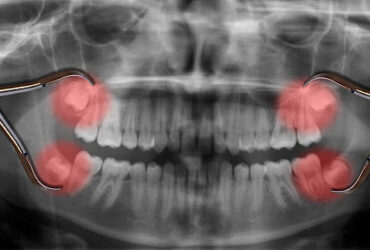

ฟันคุดคือ ฟันกรามซี่ในสุด ทั้งหมด 4 ซี่ บน ล่าง ซ้าย ขวา ไม่สามารถขึ้นได้ตามปกติเพราะพื้นที่ไม่เพียงพอให้ฟันสามารถขึ้นมาได้ บางซี่อาจจะโผล่ขึ้นมาเล็กน้อย และบางซี่ถูกฝั่งอยู่ในกระดูดขากรรไกร อาจจะขึ้นตรง เอียงหรือนอนในแนวราบส่วนใหญ่ฟันคุดมักพบว่าอยู่ที่ฟันกรามซี่ล่างในสุดและพบมากสุดในช่วงอายุ ประมาณ 16 – 25 ปี หรืออาจจะช้ากว่านั้น